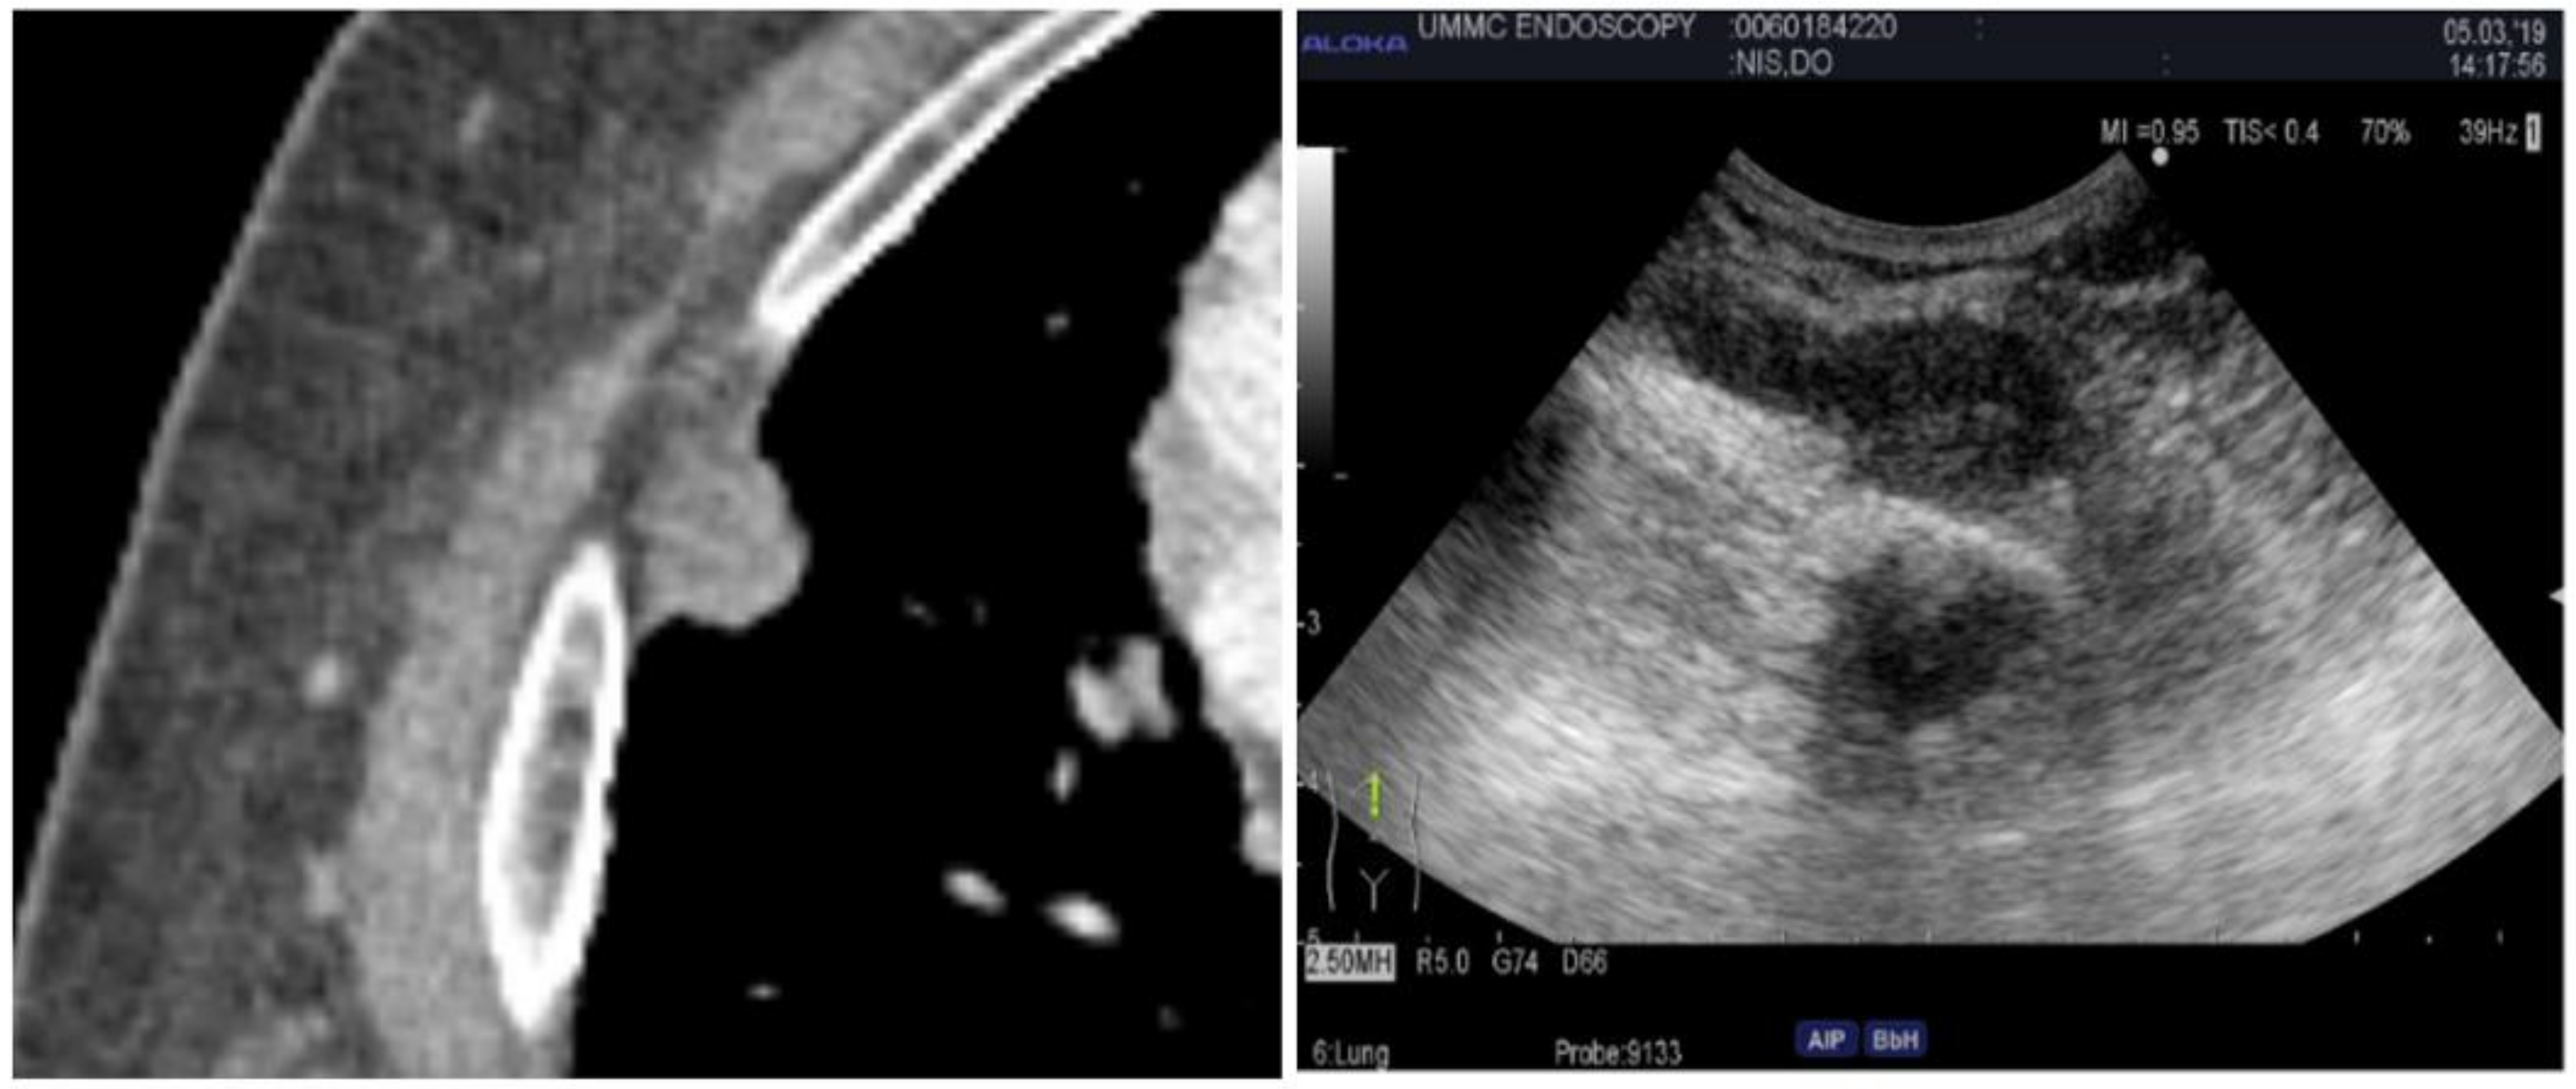

2.4. Endobronchial Ultrasound